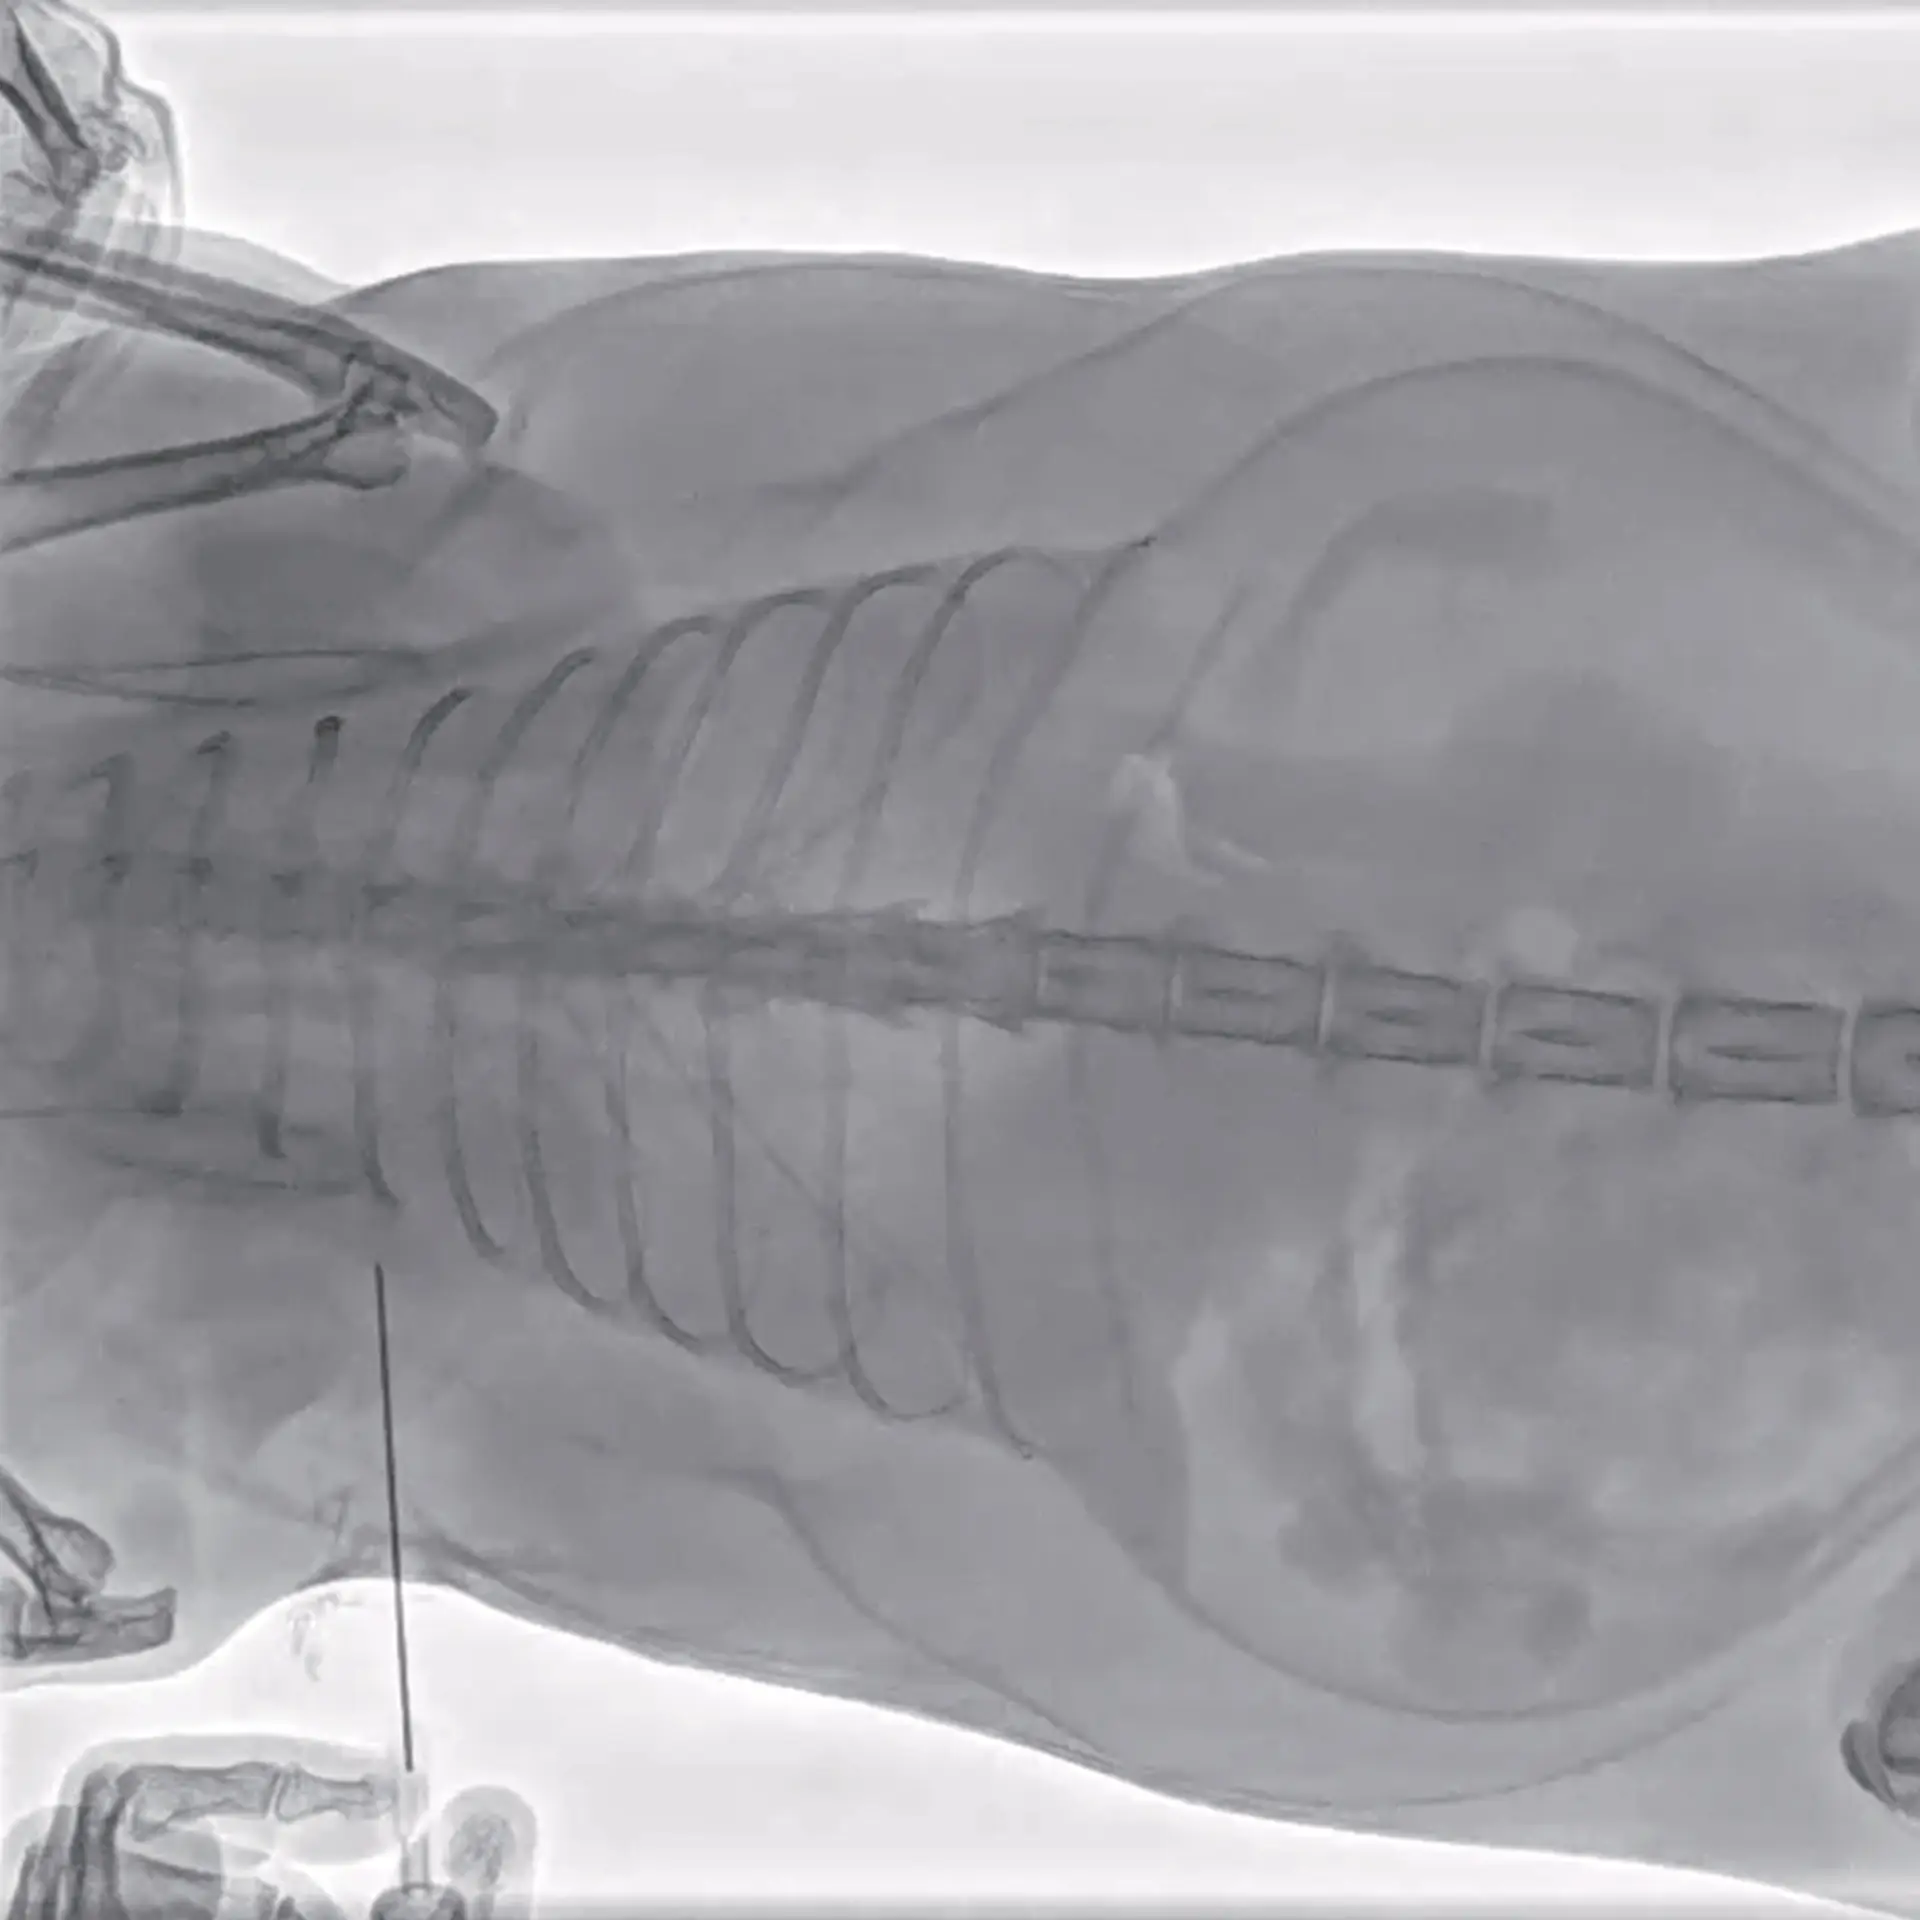

Ameliyathane